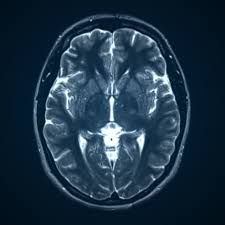

Why Is Magnetic Resonance Imaging Of The Brain Important For Early Diagnosis?

Magnetic Resonance Imaging (MRI) of the brain is a powerful diagnostic tool that helps doctors detect neurological conditions at an early stage. It provides highly detailed images of brain tissues, nerves, and blood vessels, allowing specialists to identify issues such as tumors, stroke, multiple sclerosis, or inflammation before symptoms become severe. Early diagnosis through brain MRI can help guide timely treatment and improve health outcomes. At Marris Medical UK, advanced imaging technology ensures accurate and reliable results. If you need a professional brain scan, contact Marris Medical UK today at +44 203 011 1788 to schedule your appointment.